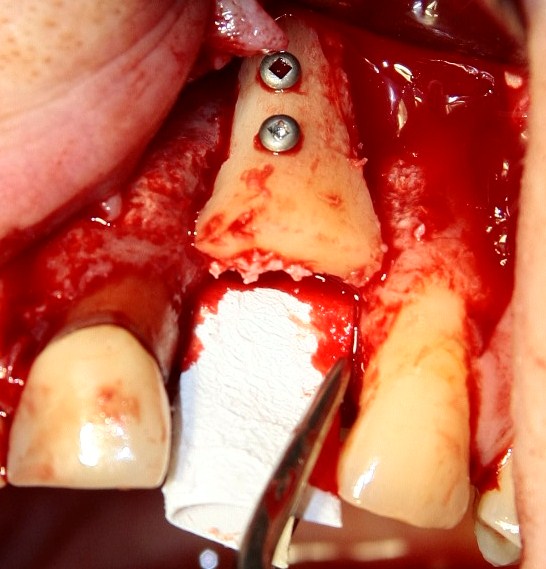

Трансплантация десны, аугментация лунки

Для определения размеров будущего мягкотканного аутотрансплантата мы использовали пародонтологический зонд. С помощью него мы выбрали донорскую зону (бугор верхней челюсти или небная сторона альвеолярного отростка верхней челюсти в области моляров), с помощью скальпеля получили необходимый по размеру аутотрансплантат (мягкотканный лоскут для пересадки).

Затем, мы подготовили ксенографт Bio-Oss Collagen. Обычно на 2 зуба (центральных резца) с избытком хватает 100-миллиграмовой упаковки. Имеющийся в ней параллелепипед мы поделили на 2 усеченные пирамиды с основанием в 2/3 ширины изначального блока.

Если вы когда-нибудь видели подобные операции, то наверняка обращали внимание на порядок действий — сначала устанавливаются имплантаты, затем укладывается графт и только потом фиксируется мягкотканный аутотрансплантат. Для удобства в этом и похожих клинических ситуациях мы поменяли порядок действий:

Сначала мы провели и зафиксировали деэпителизированный соединительнотканный аутотрансплантат (ССТ). Для этого мы сформировали тоннель и использовали ортодонтическую проволоку в качестве проводника. Подробнее об этой методике можно почитать здесь>>.

Затем уложили ксенографт. Особенностями Bio-Oss Collagen являются удобство адаптации, устойчивость к вымыванию и выдавливанию, поэтому мы просто уложили полученные ранее пирамидки вестибулярно относительно будущего имплантата, после чего прижали их с помощью уже упоминавшихся аналогов имплантата, входящих в хирургический набор имплантационной системы Xive (кстати, при работе с другими имплантационными системами для паковки графта в лунке можно использовать круглые остеотомы для синуслифтинга).

В совокупности, аугментация лунок перед установкой имплантатов занимает около 20 минут — и это самый долгий из всех хирургических этапов лечения.